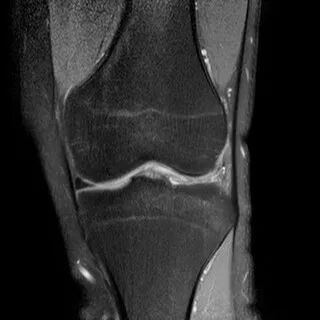

1、水平撕裂

2、较少见3、III级高信号与胫骨平台平行,到达半月板的游离缘或一侧关节面

(半月板水平撕裂)